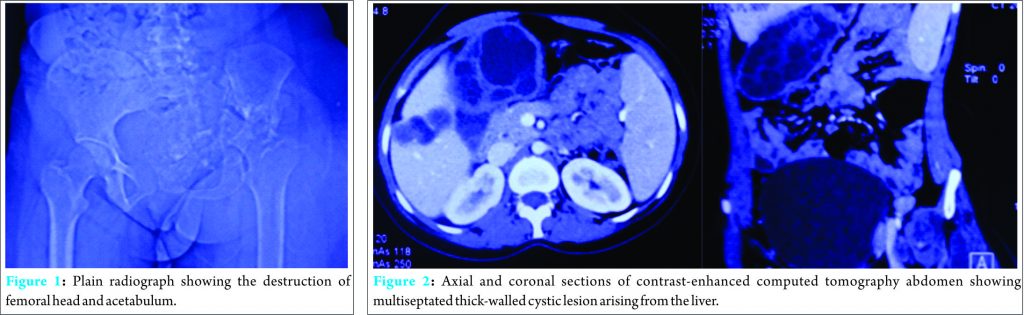

The hip was tender on palpation and associated with fullness in the iliac fossa. She had flexion deformity of 30°, with only jog of movement at the hip joint, and true shortening of 3 cm. Plain radiographs (Fig. 1) showed obliteration of joint space with the destruction of femoral head and acetabulum. Osteolytic lesions were seen in the supra-acetabular region and superior pubic ramus. Laboratory investigations revealed an elevated erythrocyte sedimentation rate (ESR) of 52 mm/h and eosinophilia, with absolute eosinophil count (AEC) of 930/mL (30-350/mL).

This prompted an ultrasound of the hepatobiliary system which revealed a well-circumscribed multilobulated lesion in segment V of the right lobe of the liver with peripheral daughter cysts. There was an associated large exophytic component extending medially beyond the hepatic capsule, suggestive of hydatid cyst. Henceforth, abdominal computed tomography (CT) scan with contrast (Fig. 2) was done revealing 10.2 cm × 5.6 cm exophytic multiseptated thick-walled cystic lesion arising from the right lobe of the liver. There was an associated smaller (3.3 cm × 2.3 cm) multiseptated cystic lesion with evidence of rim calcification. CT scan of the pelvis (Fig. 3) revealed a large multiseptated cystic lesion with the osseous destruction of the left iliac bone, acetabulum, and proximal femur. It showed complete destruction of the acetabulum with evidence of protrusio acetabuli. The cystic component of the lesion involved muscles around the hip joint and left hemipelvis. This extended into the ischiorectal fossa, gluteal region, and iliopsoas, with a cold abscess in pelvis tracking along the anterolateral aspect of the thigh. Multiple small bony fragments were seen in the cystic lesion.